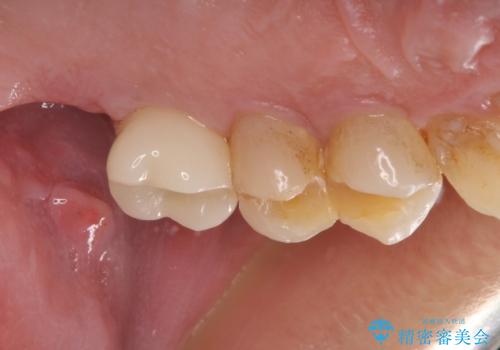

根管治療を行ったままの奥歯 オールセラミッククラウンによる補綴治療

- 以前根管治療を行い、クラウンにする必要があると言われたものの、そのままに放置してしまったとのことで来院された患者様です。

根管治療を行った歯には特に症状がないため、速やかにオールセラミッククラウンにて補綴治療を行うこととしました。

補綴治療前は食後はいつもものが挟まっていたそうですが、補綴治療後はものが挟まる悩みから解放されたとのことでした。